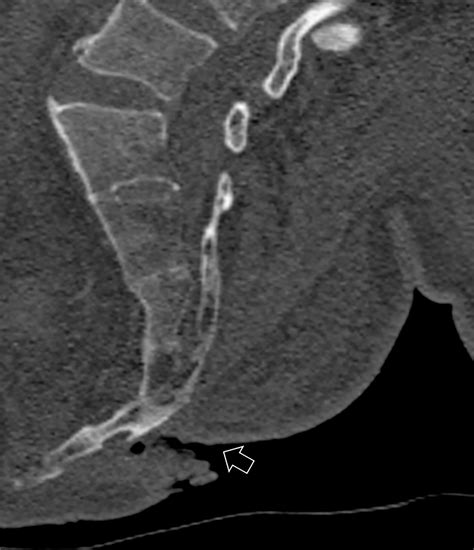

CT Scan The "gold standard" for identifying the specific plane and displacement of the sacral ala.

The proximity of the sacral ala to the sacral nerve roots makes these fractures particularly sensitive. Injury to this area can potentially affect lower limb function, bowel or bladder control, and overall mobility. Proper classification of the fracture, often determined through medical imaging, is the first step in determining whether a conservative or surgical approach is necessary.